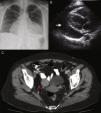

A 55-year-old woman with a history of hypertension was admitted to our institution due to severe dyspnea. On physical examination tachypnea, hypotension, and bilateral jugular distension were detected. The electrocardiogram showed sinus tachycardia. Chest radiography revealed mild bilateral pleural effusions and severe cardiomegaly (Figure 1A). An echocardiogram showed a 3-cm global pericardial effusion with signs of cardiac tamponade (Figure 1B). Due to the patient's clinical instability, drainage of the pericardial effusion was mandatory, but pericardiocentesis was unsuccessful due to catheter obstruction, and so surgical drainage was performed through a pleuropericardial window. Cytology and pericardial biopsy detected no malignant cells. Abdominal computed tomography showed ascites and a 3 cm × 4 cm ovarian fibroma (Figure 1C). Given the benign nature of the tumor, an expectant attitude was adopted.

A: Anteroposterior chest X-ray showing mild bilateral pleural effusion and massive bottle-shaped heart manifesting severe cardiomegaly; B: Two-dimensional echocardiography showing a 3-cm global pericardial effusion (arrow) and signs of cardiac tamponade; C: Pelvic computed tomography showing a right ovarian tumor, a fibroma (arrow).